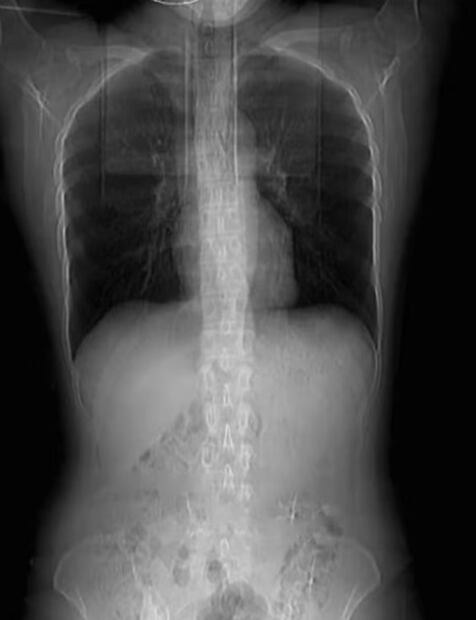

De acuerdo al medio chino South China Morning Post, una tomografía computarizada reveló que cuatro de las costillas de Huang estaban rotas ; los médicos le dijeron que necesitaría vendas alrededor de su pecho durante un mes para que sus costillas sanaran.

El portal señala, que los médicos dijeron que la causa subyacente de las fracturas menores era que su peso corporal era demasiado bajo.

La mujer, de 1.71 cm y un peso de 57 kg, dijo que es especialmente delgada en la parte superior del cuerpo y que sus costillas son visibles.

Foto: Weibo